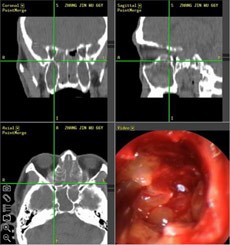

【典型案例】反复手术切息肉 复发导致嗅觉减退5年之久

张先生家住兰州,是典型的鼻窦炎患者,经常会出现鼻塞、流脓涕、头痛、等症状,去过多家医院,治疗结果并不理想,复发不说,到现在张先生的嗅觉已经严重减退,味道都快闻不出来了。

经推荐,跨省来到西安新城中大耳鼻喉医院耳鼻喉科治疗,入院后,经医生诊断并推荐使用“”,在鼻内窥镜的帮助下切除鼻息肉,术后经过10天后复诊并无复发现象。

(图为:鼻窦炎患者治疗现场)                          (图为:鼻窦炎治疗图谱)

[原理阐述]: “”技术以“CT片检查”和“STORZ鼻内窥镜”精准定位,借助“美国美敦力微创切割动力系统”和“美国杰西微创手术消融系统”  精确“扫净”四对鼻窦炎症,避免“漏诊盲区”、迁延其它鼻窦复发;同时功能性鼻腔术后修复和绿色技术,轻松清除额窦、上颌窦、筛窦和蝶窦等合并症,迅速恢复鼻部功能,治疗恢复期比同等手术缩短三倍,被称为“多窦一清”高端技术。

优势1,精确定位: “功能性鼻内窥镜系统”自带的冷光源的亮度相当于无影灯20倍,清晰的视野使治疗达到更精细的效果,3.5mm的小孔可将病变组织放大数倍,并将同步拍摄到的影象传送到相应的的电脑屏幕上,患者病变部位可被医生一览无余,可告别过去盲目凭手感和经验操作的“盲人摸象”时代。